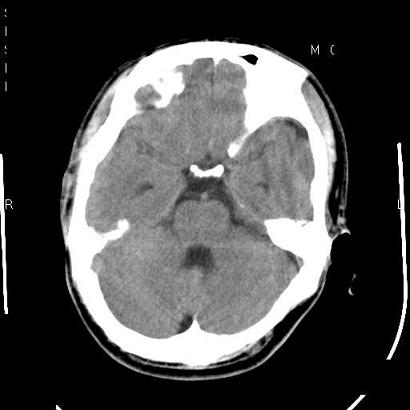

男,39岁,外伤来诊,老师们看看枕骨是什么病

枕骨静脉湖,常位于枕骨中线附近的板障间,多见于老年人,没得临床意义的。

蛛网膜颗粒压迹特点:位于中线两侧的颅骨圆形或类圆形低密度影,常多发,可融合,边缘有硬化缘,无软组织肿块。

枕内隆突左缘板障区示不规则囊状透亮区,颅骨内外板规整,无膨胀及缺损,周围无软组织肿块,考虑板障血管性病变,1.板障静脉湖,2.枕骨血管瘤(局部无膨胀性改变,无硬化环及钙斑影,故不太支持)。

蛛网膜颗粒压迹不会象这样有清晰的内板显示的!压迹压迹肯定是把内板压到板障里撒!各位老师同意不?